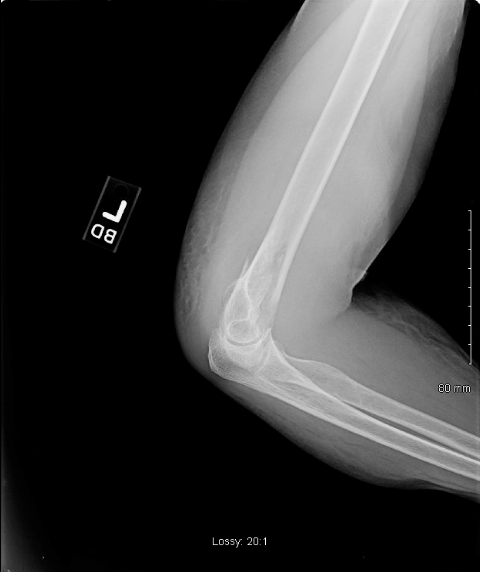

Ultrasonography is most useful for diaphyseal fractures, particularly if further imaging decision is in question. Patients who underwent unicortical medial malleolar fracture fixation between 2011 and conclusion:: Metacarpal fractures are common, accounting for 40 % of all hand injuries. John kiel on 30 june 2019 19:53:38. Unicortical fracture or incomplete fracture: (a) pa view and (b) lateral views show a unicortical fracture of the. The use of plates for the fixation of these fractures allows plating of metacarpal fractures: Fractures of the scaphoid, the radial styloid, and the rst metacarpal often result in displacement or figure 39 torus fracture. Metacarpal fractures are common, accounting for 40 % of all hand injuries. Her fracture was successfully fixated with an intramedullary nail with retention of the knee prosthesis. .avulsion fractures in young athletes, whether to use unicortical or bicortical fixation is debatable. Fractures of the knee include fractures of the patella, femoral condyles, tibial eminence, tibial tuberosity and tibial plateau. This trial aims to compare fracture union, complication rate and functional outcomes between unicortical and bicortical fixation for adults with displaced metacarpal fractures. Failure to detect injury can lead to catastrophic fracture. Clinical findings associated with unicortical condylar fractures can be mild and appropriate diagnostic imaging is necessary for injury detection. It was possible to add a unicortical. Unicortical locking plate fixation of metacarpal fracture can be reliably applied clinically to produce a strong and stable construct that allows early mobilization of the joints.